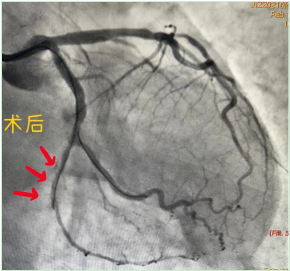

齐峰主任听闻老人家生病以前耳聪目明,平常生活能自理,年前1个月发生了急性心肌梗死,外院就诊,考虑患者年龄大,拒绝为其手术,一直给予药物保守治疗,经过一个月双联抗血小板药物治疗,患者也未出现各种出血并发症,这次生病之后,稍微活动就有心绞痛症状发作,结合患者病史及外院的检查结果,决定为其行PCI手术,开通他的“生命之路”,术中尽量无植入,避免术后出现出血等并发症。老爷爷住进云南阜外医院冠心病一病区,温馨的病房,干净整洁的病床,关爱有加的医护团队,给爷爷制定了周全的诊疗计划。住院期间,从生活上关心,防止爷爷摔跤跌倒,坠床,护理姐妹做出了巨大贡献,医疗方面,主治医师完善术前检查,评估手术指征,外周血管CTA检查明确冠脉介入手术入路,避免在手术过程中,为老爷爷带来操作风险,术中的精心操作,术后的治疗,在冠心病一病区这个团队,都得到了充分体现,给予病人精心护理,精准治疗,让病人获益匪浅。

经皮冠状动脉介入治疗( percutaneous coronary intervention,PCI),是指经心导管技术,疏通狭窄甚至闭塞的冠状动脉管腔,从而改善心肌血流灌注的微创手术治疗方法。